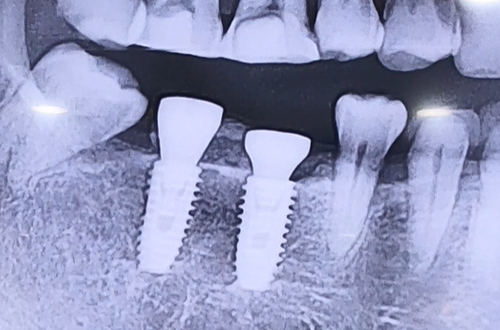

발치한지 오래된 오른쪽 아래 어금니 두 개를

회복시키기 위한 임플란트를 위해 내원하신 환자분이십니다.

때문에 CT촬영을 통해 정확한 잇몸뼈 모양과 구조를 파악하고

임플란트를 진행한, 조금 특수한 케이스였습니다.